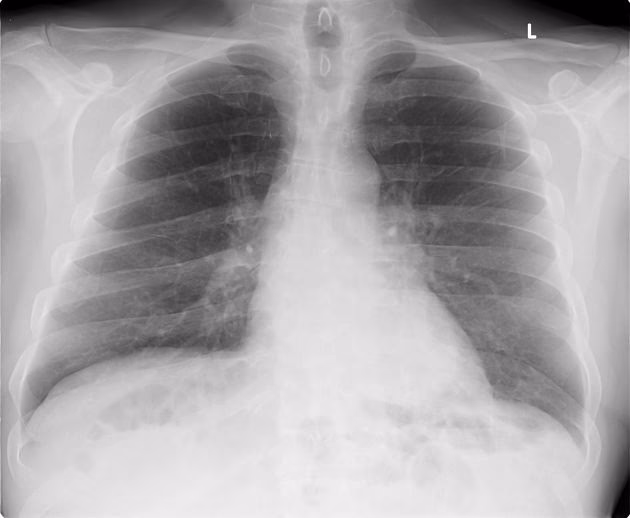

Esta afección inflama los sacos de aire en uno o ambos pulmones, conocidos como alvéolos. En respuesta a la infección, estos sacos pueden llenarse de líquido o pus, lo que dificulta la respiración y provoca síntomas como tos con flema, fiebre, escalofríos y dificultad para respirar. La neumonía puede ser causada por una variedad de microorganismos, incluyendo bacterias, virus y, menos comúnmente, hongos.

Como mencionamos, la neumonía es una infección que inflama los pequeños sacos de aire dentro de los pulmones (alvéolos). Normalmente, estos alvéolos están llenos de aire, permitiendo el intercambio de oxígeno y dióxido de carbono. Cuando hay neumonía, se llenan de líquido o pus, lo que interfiere seriamente con esta función vital. La gravedad de la neumonía puede variar considerablemente, desde leve, similar a un resfriado o gripe fuerte, hasta potencialmente mortal, especialmente para ciertos grupos de riesgo.